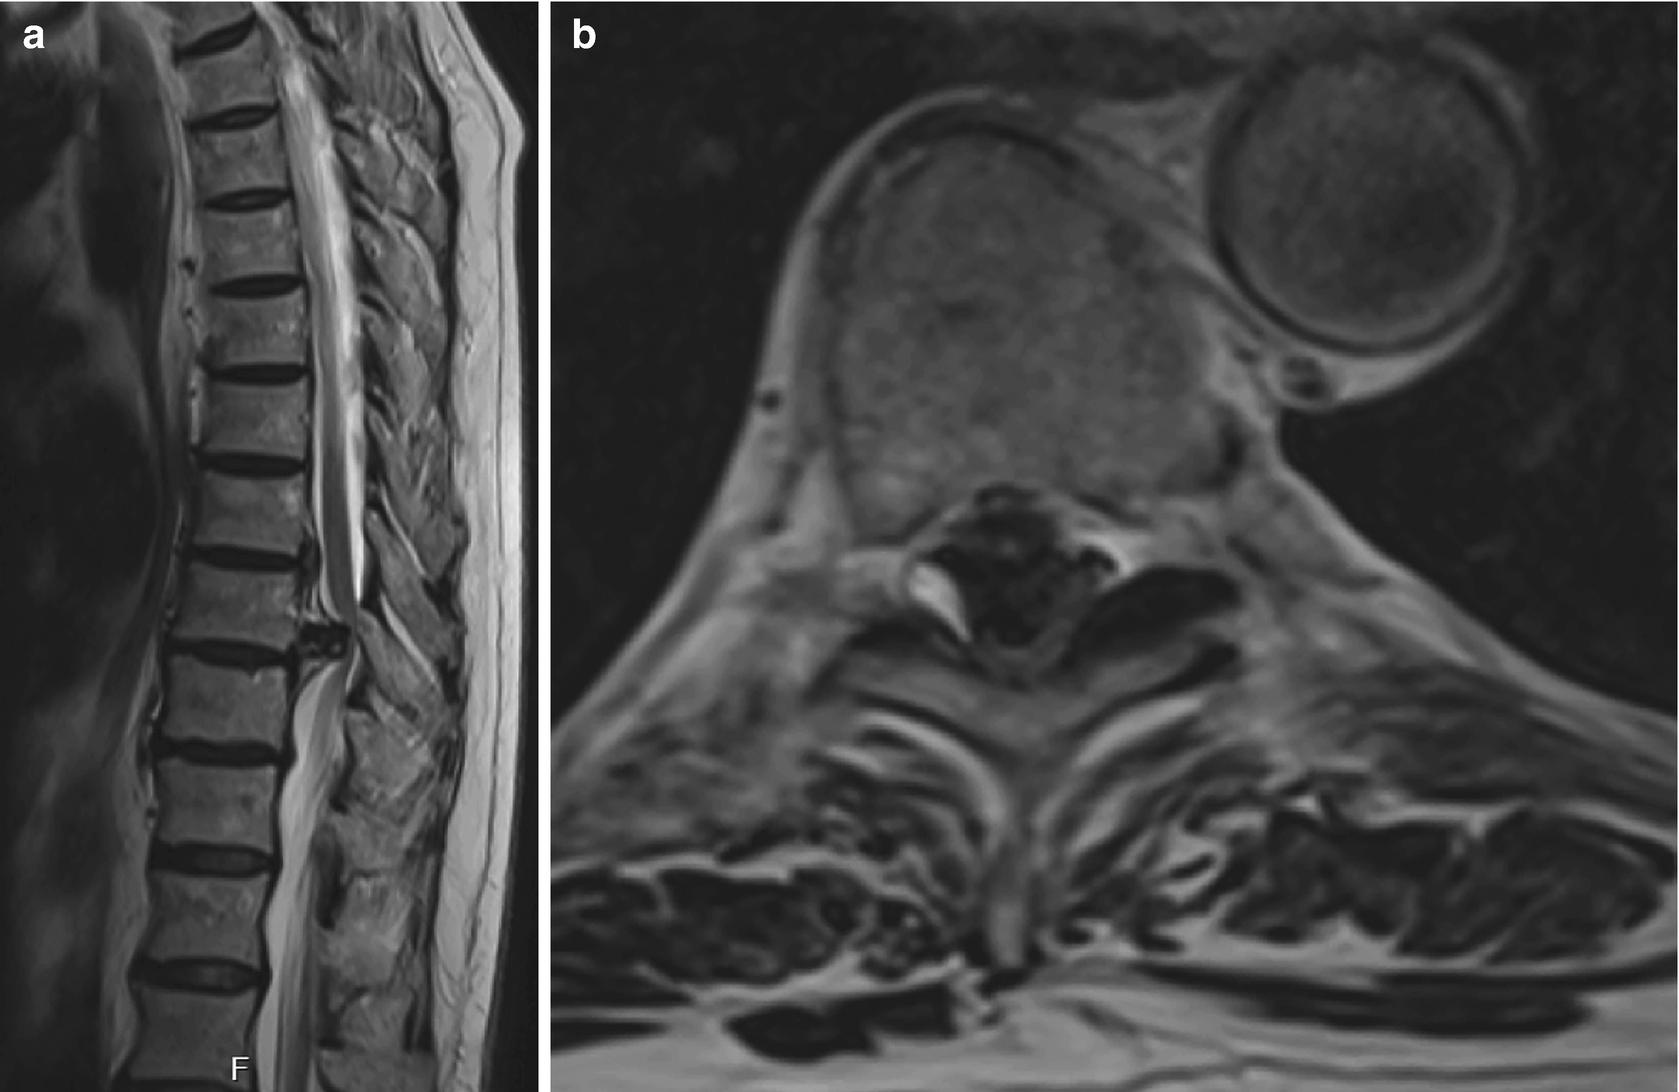

Typical case 1. A 35‐year‐old male patient with myelopathy caused by Disc Herniation Myelopathy Symptoms Degenerative cervical myelopathy is a condition that is caused by age related changes to the bones, ligaments and discs of. Spinal compression from overgrown bone or ligaments, disc herniation, intrinsic and. When the discs between the vertebrae bulge or break, pressing on the spinal cord. Typical symptoms for each include: There are many possible causes of myelopathy: Thoracic myelopathy causes. Disc Herniation Myelopathy Symptoms.